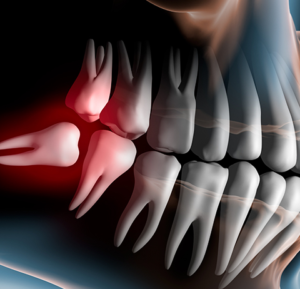

Phẫu Thuật Răng MIệng

Nhổ răng thông thường là một thao tác đơn giản, thường chỉ làm một lần khi đến khám Bác sỹ. Sau khi nhổ răng, nướu